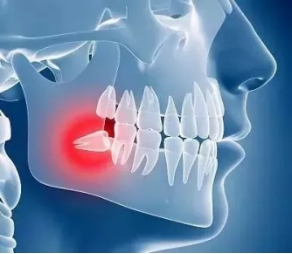

(二)准妈妈的智齿问题

刚才提到了激素水平变化会让您的牙龈更容易发炎,如果您又碰巧有一颗埋伏的阻生智齿,那孕期就更容易发生智齿周围的牙龈发炎肿胀。当然,这也和孕期人体的抵抗力降低有关。

经历过智齿发炎的人一定了解其中的苦楚。如果在孕期的话,您因为担心宝宝健康不敢随意用药,又吃不下饭不能摄入充足的营养,可谓危害多多。淤积的食物残渣易造成细菌过度繁殖导致周围的牙龈和软组织出现的红肿胀痛,吞咽困难,张口受限而影响进食,严重的还可能引发面部多间隙感染,也会对胎儿健康造成影响。再次提醒打算备孕的姑娘们,一定要提前完善口腔检查及治疗,一定要在孕前把阻生智齿拔掉,以除后患,以健康的身体、灿烂的笑容迎接宝宝的到来。